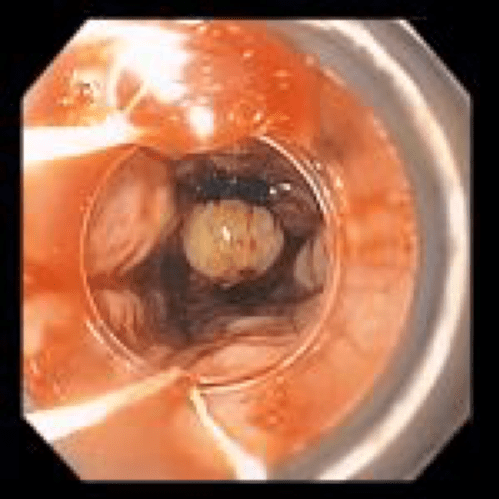

Therapeutic procedures that can be done during endoscopy are:

- Polyp removal

- Dilatation of strictures